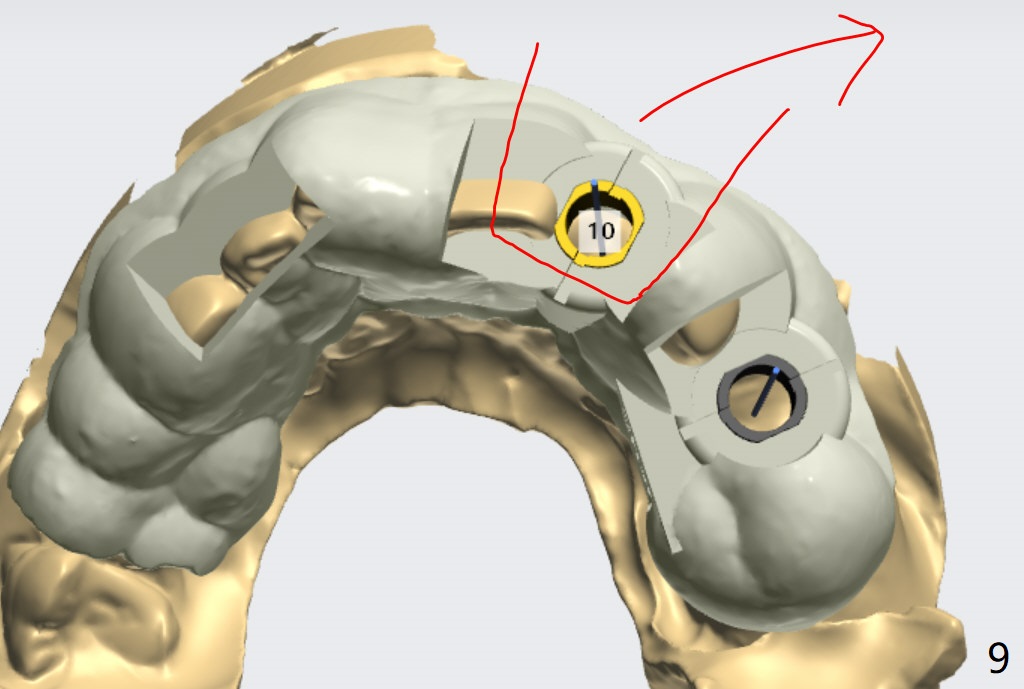

The patient has gummy smile (Fig.1).  The edentulous ridge at #10 has buccal concavity (Fig.2 *).  The surgical guide fits well without #9 distal trimming.  With 34 mg Xylocaine and 17 mcg Epinephrine infiltration at #10 and 12, the patient feels pain when 2.2 (in fact 1.9) x8.5 mm drill is being used.  When Septocaine is added, the osteotomy at #10 is found distal.  Out of curiosity, PA is taken with 2.2x10 mm drill in place; its trajectory seems satisfactory (Fig.3).  When a 2.5x13 mm 1-piece implant is placed free hand, it deviates palatal, which is confirmed with incision after addition of 34 mg Xylocaine and 34 mcg Epinephrine.  A new osteotomy is created by S-Mini Kit buccal to the previous one.  With Lindamann bur to adjust the position of the new osteotomy twice, the last drill (2.0 mm) apparently starts to perforate the apical portion of the buccal plate.  The perforation seems to enlarge when the mini implant is re-placed (Fig.4, 8 (green area) <30 Ncm).  With Vanilla graft (Fig.8 pink circles) and abutment height adjustment (Fig.4), a provisional is fabricated with occlusal clearance.  There are two reasons for failure of the surgical guide: failure to trim the tooth #9 distal (minor palatal guide displacement, Fig.5) and deflection of pointed drill and 2.2 mm drills over the hard palatal plate slope (Fig.6).  To avoid this complication, the pointed drill should be done free hand initially, after incision and obliquely (Fig.7).  The guide is placed to finish the rest of osteotomy if deem to be appropriate.

And I can cut it but also you can cut it with the high speed bur at the char. Please see the attached screenshot (Fig.9).